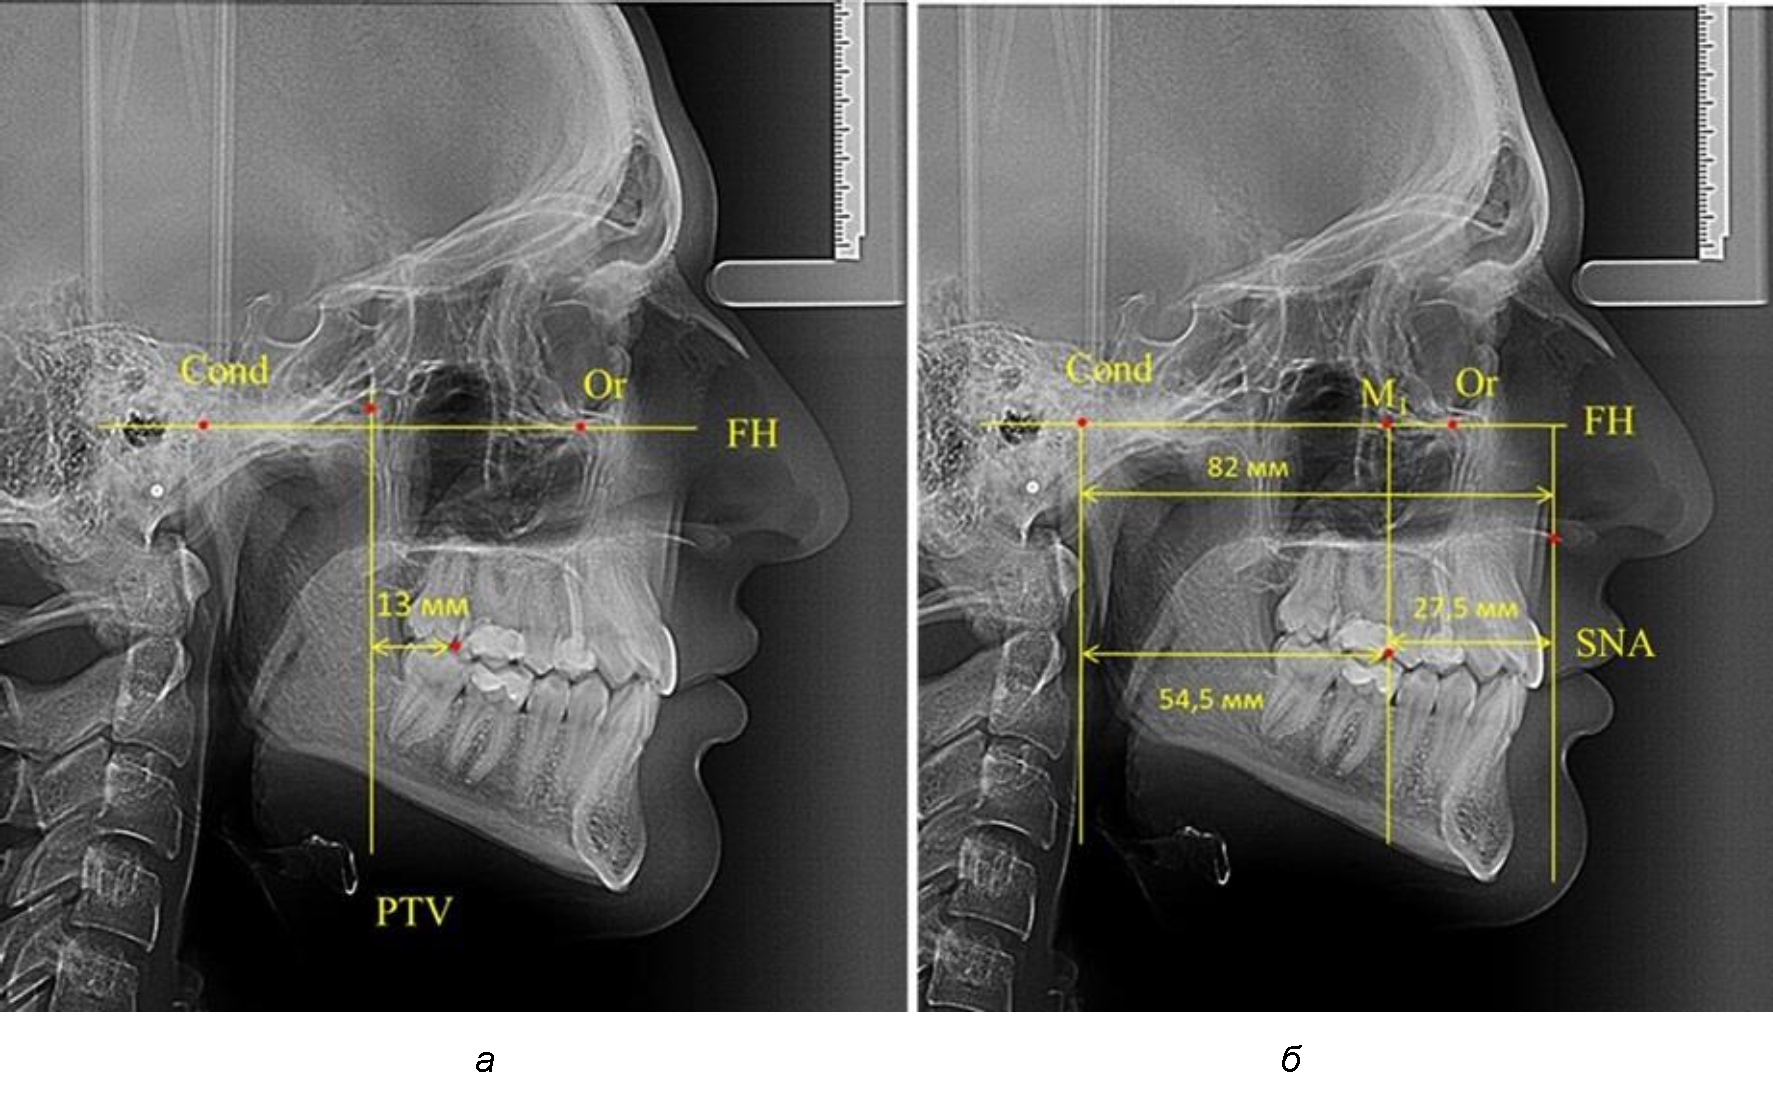

Так, при расстоянии от крыловидной вертикальной плоскости PTV до дистальной поверхности верхнего первого постоянного моляра в 13 мм сагиттальный размер гнатического отдела был 82 мм. При этом отношение кондилярно-спинального расстояния к кондилярно-молярному размеру (54,5) было близким к коэффициенту 1,5, что представлено на рис. 2.

Рис. 2. Особенности положения первых моляров по R. E. McDonald (а) и по предложенному методу (б) при уменьшенном молярно-крыловидном расстоянии

Рис. 3. Особенности положения первых моляров по R. E. McDonald (а) и по предложенному методу (б) при увеличенном молярно-крыловидном расстоянии